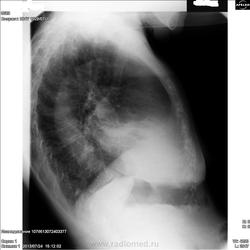

А, все-равно придется строить. Во-первых, бабушка дышала; во-вторых, на среднюю (и нижнюю) доли, лучше делать боковые томограммы; в-третьих, прямые томограммы (при подзрении на онко), лучше делать с центрацией на корень (а не тень) и обязательно начинать с срединного среза; ну, и в четвертых, нарушения проходимости среднедолевого бронха, как правило, требуют бронхоскопии (даже после КТ).

Среднюю долю показательнее резать на боку. Насчет полости распада: она есть (в прямой проекции - явно, в боковой  - с уровнем/черные стрелки, или может ниже/красные стрелки).